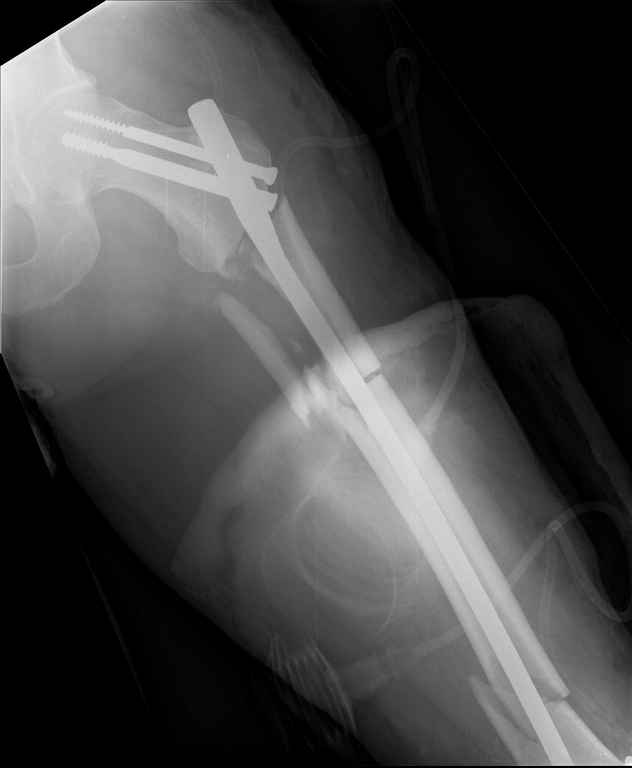

Ds: ТСТ. ЗЧМТ. СГМ. ЗТГК. О/фрагментарный перелом левого бедра. З/оскольчатый перелом с\3 левого плеча. Перелом левого локтевого отростка. З/перелом наружного мыщелка б/берцовой кости в/3 м/берцовой кости левой голени. при поступлении, ПХО раны левого бедра( рана 1х1см по наружной поверхности бедра в с/3) налажено скелетное вытяжение , и гипсовая лонгета на левую в/конечность. Находился в реанимации. 17.02.11 был прооперирован: БИОС левого плеча, о/синтез левого локтевого отростка по Веберу, БИОС левого бедра (длинная версия Fi-Can Sanatmetal диаметр 10мм), мыщелок голени трогать не стали.при остеосинтезе бедра возникли трудности при закрытй репозиции перелома в н/3, в связи с чем решили открыться внизу , отрепонировали без особого труда и выполнили блокирование во фронтальной плоскости 3-мя винтами + 1 винт спереди гвоздя (промазал). Убрал костодержатель, все нормально, контроль ЭОПом стояние отломков нормальное, зашились. На контрольной R-мме на утро выявлено вторичное смещение дистального отломка. Левая нога по сравнению со здоровой удлиннена до 2,5см( это за счет вальгусной установки гвоздя в проксимальном отделе, боялся свалиться на варус). Теперь думаем как поправить положение отломков в н/3, и зафиксировать так чтобы не съехало. Наше предложение расшиться в н/3 бедра, разблокироваться, перелом отрепонировать вновь и установить 1или 2отклоняющих винта в сагитальной плоскости, затем заблокироваться во фронтальной плоскости снова. Помогите советом, как выйти достойно из сложившейся ситуации. Заранее спасибо.

С моей точки зрения удлинение (если таковое имеется) произошло не за счёт вальгусной установки стержня. На контрольной рентгенограмме блокирующие винты точно расположены в шейке бедренной кости и в центре ротации головки. И даже если выбран стержень с максимальным из выпускаемых углом в 135 градусов, он не обеспечит столь значительного удлинения конечности. Увеличенный шеечно-диафизарный угол на контрольной рентгенограмме со стержнем объясняется наружной ротацией конечности при рентгенографии и возникающем при этом проекционном искажении ШДУ. Скорее всего, удлинение конечности объясняется наличием диастаза между отломками в вертельной области.

> - Убрал костодержатель, все нормально, контроль ЭОПом стояние отломков нормальное, зашились. На контрольной R-мме на утро выявлено вторичное смещение дистального отломка.

Важно установить из-за чего произошла вальгусная деформация дистального отломка (при условии, что на операционном столе после дистального блокирования её не было). Если взять в руки стержень и ввести в дистальное круглое отверстие блокирующий винт, то из-за разности в диаметрах блокирующего винта и диаметра блокирующего отверстия в стержне, возможно отклонение стержня во фронтальной плоскости до 13 градусов в каждую из сторон. Если второе отверстие для блокирования на дистальном конце стержня круглое, проблема «качания» дистального отломка во фронтальной плоскости на одном блокирующем винте при инфраистмальных переломах решается введением второго блокирующего винта во фронтальной плоскости. Если второе блокирующее отверстие овальное, введение второго блокирующего винта во фронтальной плоскости эту проблему не решит (кажется, это ваш случай). В таком случае лучшим решением является введение блокирующего винта в сагитальной плоскости через соответствующее отверстие стержня (это всегда лучший вариант). Однако в выбранном стержне такого отверстия нет. Поэтому мы бы поступили следующим образом. Удалили бы все дистальные блокирующие винты. Выполнили бы открытую репозицию дистального перелома на стержне с ликвидацией вальгусной деформации. Мне представляется, что это технически выполнимо, поскольку стержень не погружен в мыщелки глубоко и уже произошло вторичное смещение. Перелом предварительно фиксировали бы костодержателем. В качестве противоупора в заглушку стержня необходимо вставить отвёртку. Ударами по костодержателю в проксимальном направлении постарались бы ликвидировать диастаз в вертельной области. Выполнили бы дистальное блокирование двумя винтами во фронтальной плоскости, причём винт в овальном отверстии провели бы по его проксимальному краю. На проксимальном конце дистального отломка максимально близко к месту перелома в сагитальной плоскости провели бы два винта poler по обеим сторонам стержня.